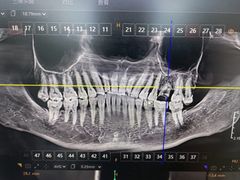

• 牙博士口腔品牌连锁(杨浦店)

• -牙博士口腔品牌连锁(杨浦店)